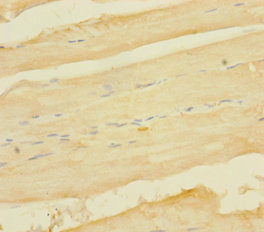

ApplicationELISA, IHC; Recommended dilution: IHC:1:20-1:200